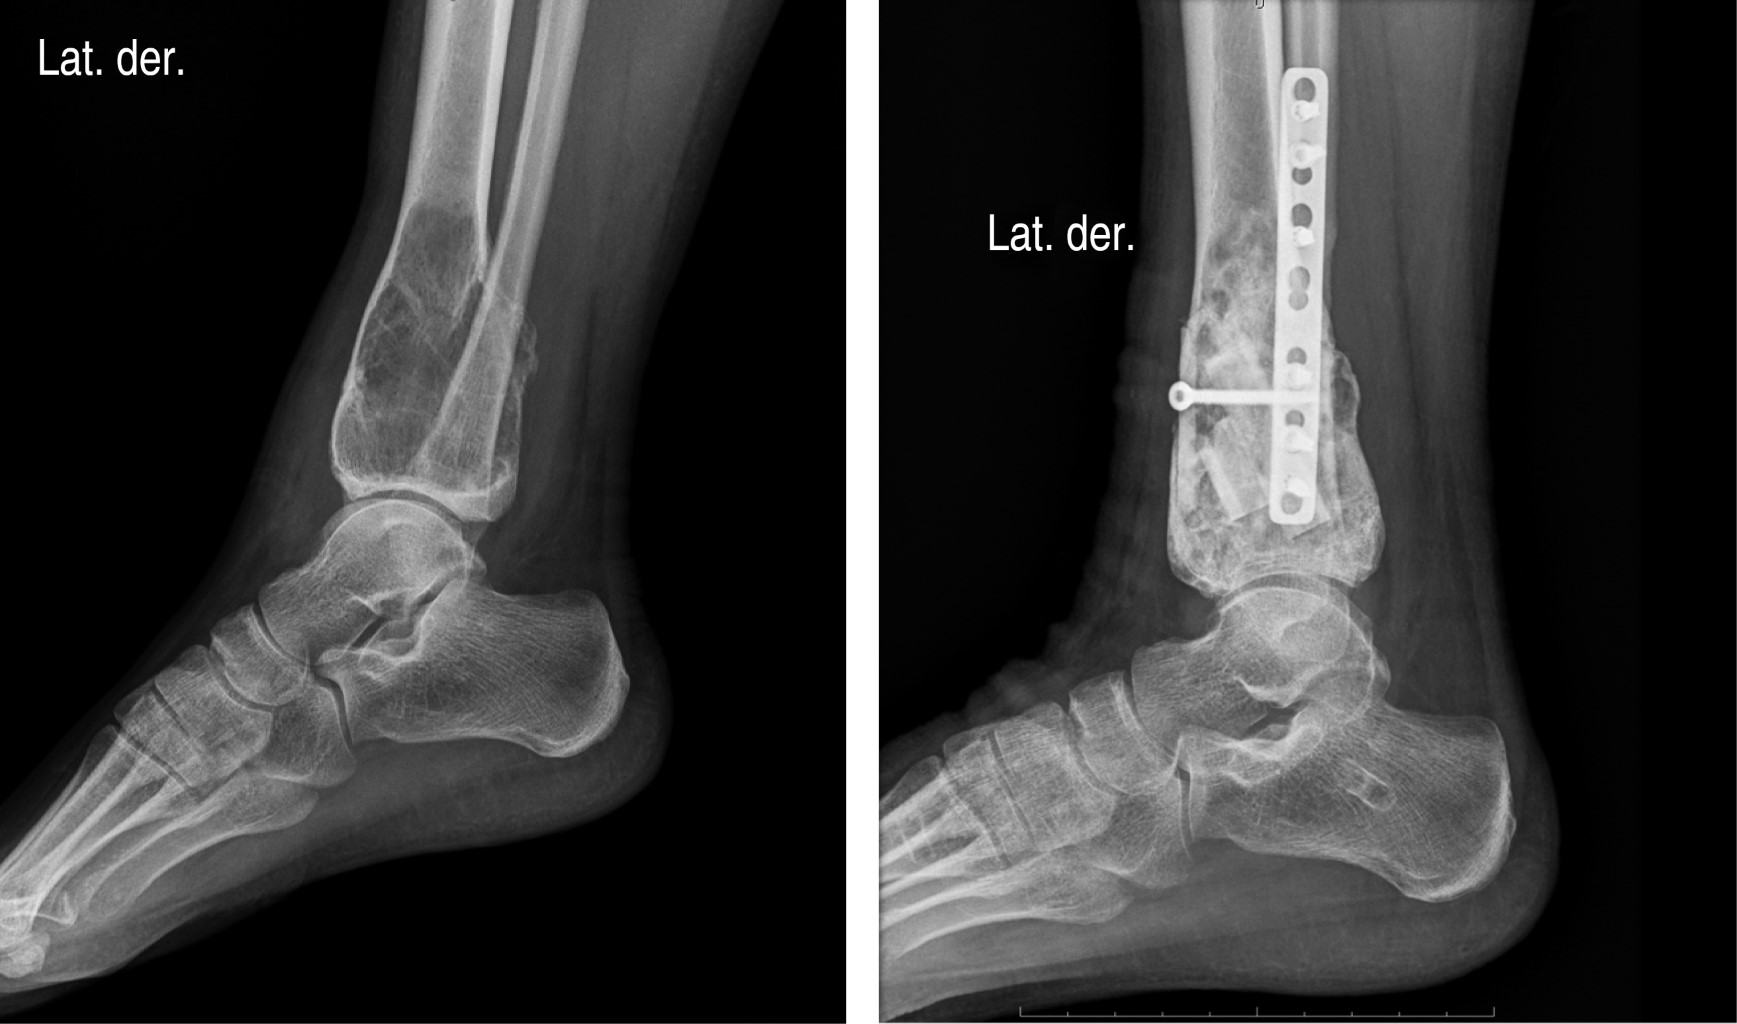

Caso 4. Paciente femenino de 32 años que, a consecuencia de dolor en el tobillo derecho, se le solicitaron radiografías convencionales en las que se identificó una lesión osteolítica metaepifisaria en la tibia distal. Los estudios complementarios mostraron una lesión osteolítica con integridad cortical y niveles hídricos en su interior. Se programó para biopsia; sin embargo, dos días previos a dicho procedimiento sufrió caída y se ocasionó una fractura tibioperonea en la metáfisis distal a nivel de la lesión descrita. Se pasó a fijación externa de la lesión y la toma de biopsia, la cual reportó quiste óseo aneurismático. Al tratarse de una neoplasia que ha perdido su integridad cortical, se tomó la decisión conjunta de dar tratamiento con denosumab, el cual se administró únicamente en dos ocasiones 120 y 60 mg, respectivamente, pese a que la indicación había sido diferente. La fijación externa se continuó por tres meses y posteriormente se realizó el retiro de la ésta, se procedió a la colocación de placa de osteosíntesis en peroné y la resección intralesional con aporte de aloinjertos en forma de diáfisis de peroné liofilizado y chips cortico-esponjosos en el interior de la lesión. La ventana ósea se cerró con un pequeño strut de la misma diáfisis y se fijó con un tornillo. La movilidad del tobillo se buscó desde el postoperatorio inmediato, lográndose en su totalidad un mes más tarde. El soporte de carga se inició a los tres meses y se permitió totalmente a los cuatro (Figura 4).

Figura 4